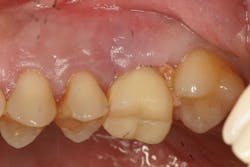

Figures 7-9: Implant site No. 19 has been restored for one year without any incident of screw loosening. Bone levels are excellent (figure 7), but a small gap is evident between the abutment and fixture platform upon radiographic evaluation (figure 8), due to the usage of implants from two "compatible" manufacturers. The tissue levels are excellent, despite a "mismatch" in components. Notice the gingival recession and the lack of attached tissue15,16 on distal implant site No. 18 (figure 9). However, with critical examination of implant No. 18, it is possible that the transmucosal element is too long and the overlying gingival tissues too thin, making this particular fixture inappropriate for this site. (Perhaps a bone-level fixture would have been a better choice.)